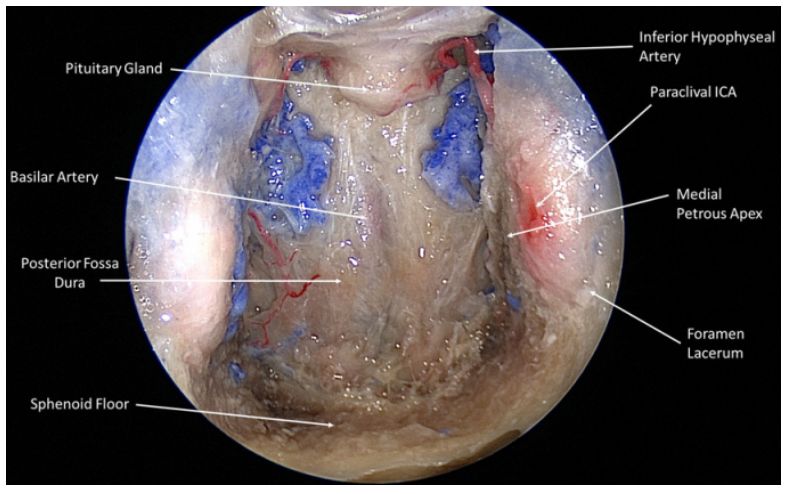

27.内镜下扩大经对侧上颌间隙至岩尖入路

Contralateral transmaxillary corridor: an augmented endoscopic approach to the petrous apex.

PMID: 29053078 DOI: 10.3171/2017.4.JNS162483

内镜下经鼻入路(endoscopic endonasal approach, EEA)处理岩尖病变是一种有效方法。岩尖外侧至颈内动脉(internal carotid artery, ICA)斜坡旁段病变需要将ICA斜坡旁段轮廓化或经翼突眼下入路处理。研究通过影像导航、EEA和扩大对侧上颌间隙(contralateral transmaxillary , CTM)对5例尸头进行解剖研究,切除海绵窦前壁和喙突,从手术角度对ICA岩段进行测量。结果显示,标准内镜下扩大CTM至岩尖可以提供更靠外侧的手术径路,可以减少与ICA斜坡旁段操作相关的风险和并发症。

【李信晓】